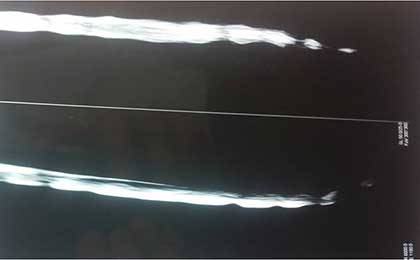

MYELO OF SEQ DISC 3